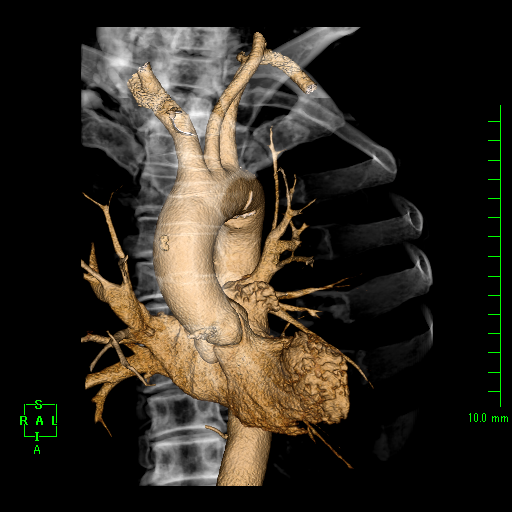

| 冠動脈CT検査 |

造影剤を使用し、心臓の血管(冠動脈)を撮影します。心臓は拍動しているので、心電図と同期させ高速に撮影します。 撮影した画像をワークステーションで処理することで、冠動脈の3D画像を作成したり、冠動脈の状態を確認できます。主に冠動脈の狭窄が疑われる患者様に行います。 |